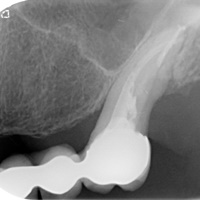

Po urwaniu narzędzia w zębie, endodonta odstąpił od leczenia kanałowego. Wykonano resekcję. Na RTG widoczne dobre gojenie tkanek kostnych, niewidoczna blizna na dziąśle.